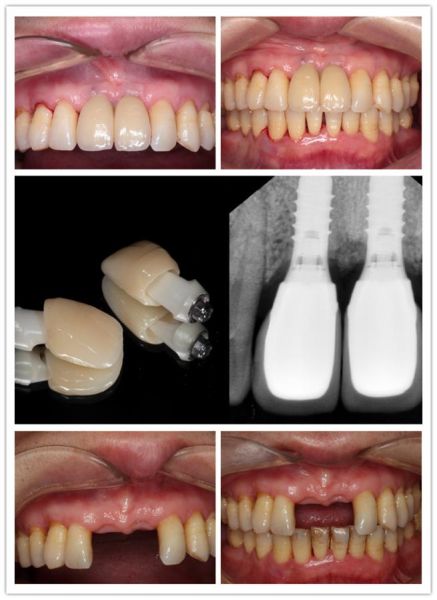

重度牙周炎种牙图片,重度牙周炎图片

图26 翻瓣后发现骨缺损,种植牙牙周炎

重度牙周炎的治疗——典型病例之一